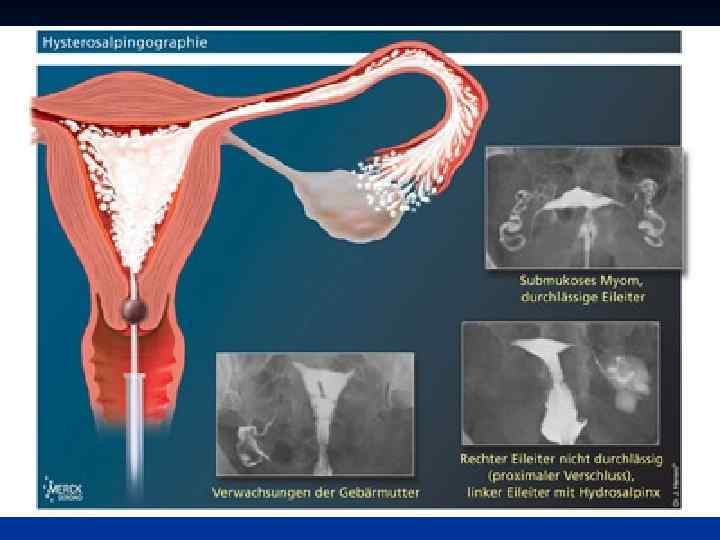

Рис 1 (норма) Гистерограмма: 1 — перешеек матки, 2 — канал шейки матки, 3 — катетер, через который введено рентгеноконтрастное вещество; видно значительное расширение перешейка и канала шейки матки. Рис 2 И стмико-цервика льная недоста точность (insufficientia isthmicocervicalis; Истмико+ анат. cervix uteri шейка матки) -нарушение функции шейки и перешейка матки, проявляющееся зиянием шейки матки, приводящим к самопроизвольному прерыванию беременности; возникает в результате повреждения миометрия или при нарушении гормональной регуляции.

Рис 1 (норма) Гистерограмма: 1 — перешеек матки, 2 — канал шейки матки, 3 — катетер, через который введено рентгеноконтрастное вещество; видно значительное расширение перешейка и канала шейки матки. Рис 2 И стмико-цервика льная недоста точность (insufficientia isthmicocervicalis; Истмико+ анат. cervix uteri шейка матки) -нарушение функции шейки и перешейка матки, проявляющееся зиянием шейки матки, приводящим к самопроизвольному прерыванию беременности; возникает в результате повреждения миометрия или при нарушении гормональной регуляции.